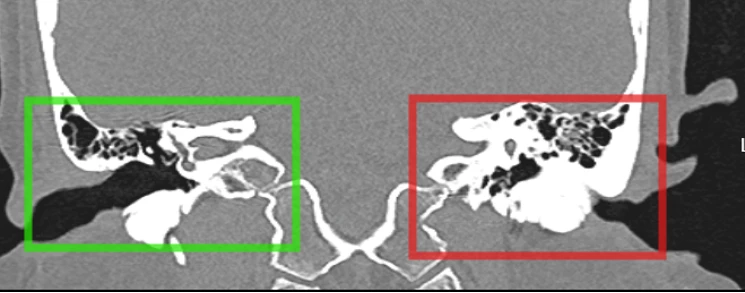

Hình ảnh khối đậm độ như xương với các thành của ống tai xương, lan vào ống tai ngoài, làm chít hẹp gần như toàn bộ ống tai ngoài trái, đọng ít dịch trong phần ống tai ngoài chưa bị chít hẹp. Ảnh: BVCC

Thăm khám tại Bệnh viện TP Thủ Đức, bệnh nhân được chẩn đoán xác định bị lồi xương ống tai ngoài - một bệnh lý hiếm gặp, đặc biệt ở bệnh nhân nữ không có tiền sử tiếp xúc thường xuyên với nước lạnh.

Theo bác sĩ chuyên khoa II Lâm Thế Phương, Phó Trưởng khoa Tai Mũi Họng Bệnh viện TP Thủ Đức, qua thăm khám chi tiết và chụp CT xương thái dương, bác sĩ phát hiện một khối đậm độ như xương, kích thước lớn, gây chít hẹp gần như toàn bộ ống tai ngoài bên trái.